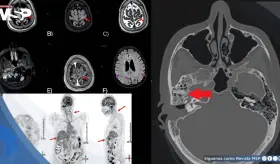

Las lesiones óseas osteolíticas, anemia y alteraciones hematológicas h...

Aunque incurable, esta neoplasia de células plasmáticas ya se controla de forma crónica gracias a innovaciones como anticuerpos monoclonales y terapias CAR-T, accesibles en Puerto Rico

Especialista explica qué es esta malignidad de células plasmáticas, cómo se detecta y por qué los avances en tratamientos han transformado radicalmente el pronóstico de los pacientes.